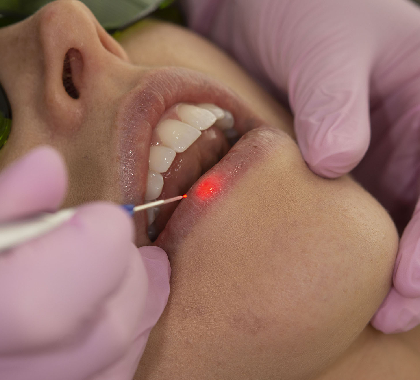

Single Sitting Root Canal

Efficient, painless single sitting root canal treatment, utilizing advanced techniques for quick recovery, saving time without compromising on quality dental care.

Vein treatment (root canal)

Root canal therapy, a vein treatment, expertly addresses infected dental pulp, relieving pain, saving teeth, and restoring oral health with precision and care.

Root Canal Treatment

A dental procedure involving the removal of the soft center of the tooth, the pulp.